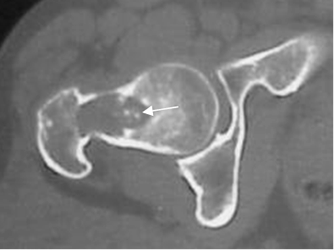

Fig 82. Condroblastoma.

A: Rx lateral y B: TAC axial. Lesión lítica y epifisiaria en la tibia proximal, con calcificaciones puntiformes de origen condroide, por condroblastoma.